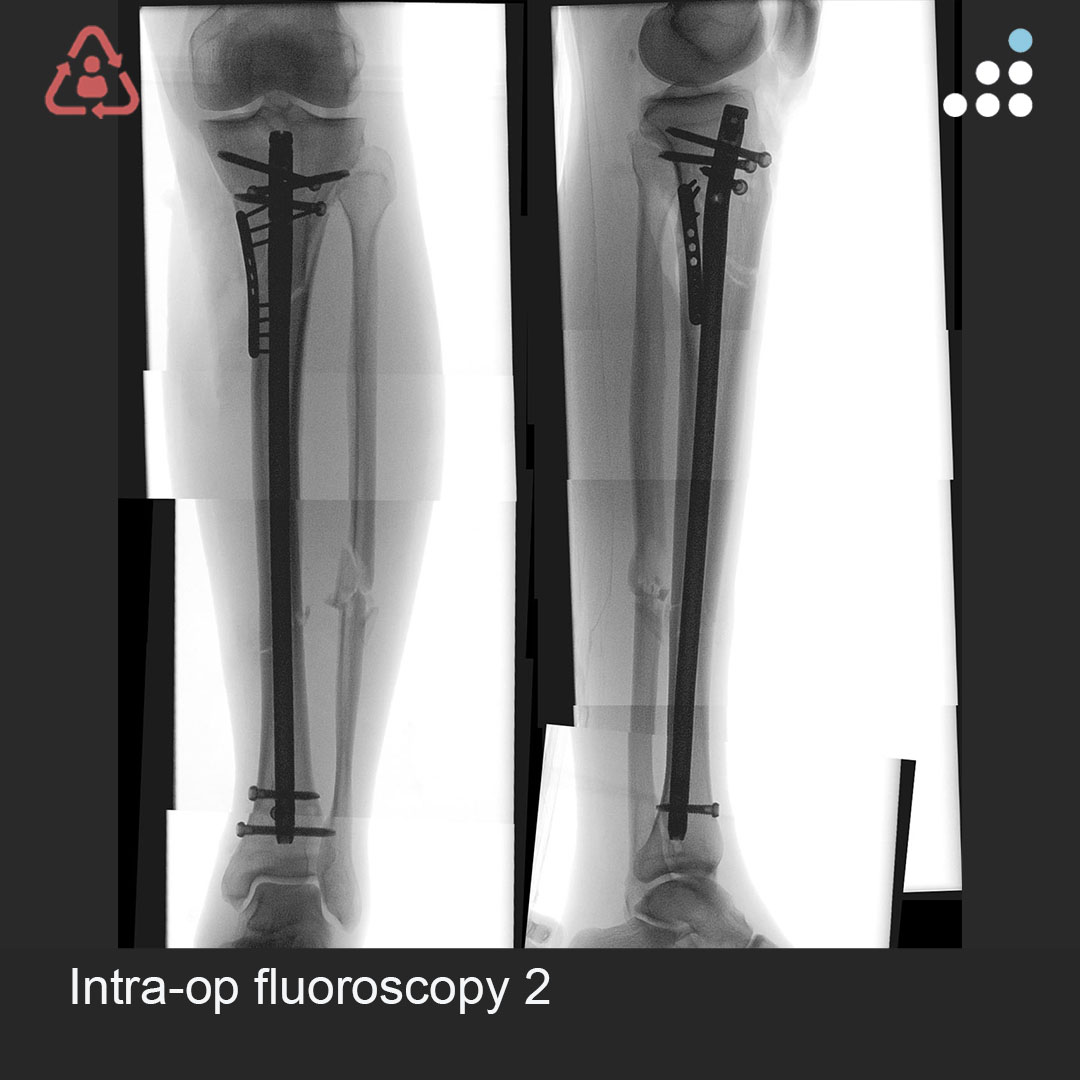

Here is a new case by Dr. Simon Donald and Queensland Health Bundaberg Hospital (@qldhealth). PROXIMAL SEGMENTAL TIBIAL FX S/P MALREDUCED IMN IN 58M How would you manage this #orthotwitter? Vote on this case for CME: orthobullets.tiny.us/4z6wm3rx